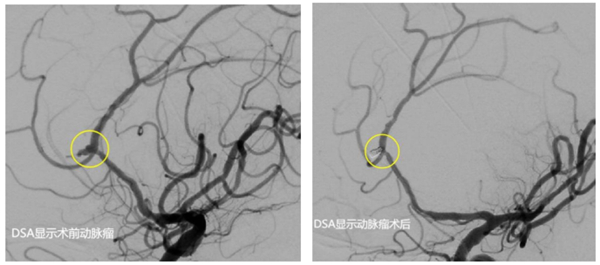

經(jīng)和家屬協(xié)商,同意進(jìn)行手術(shù)。該院神經(jīng)外科介入團(tuán)隊(duì)立即啟動(dòng)手術(shù)預(yù)案。麻醉醫(yī)師、手術(shù)室護(hù)士、導(dǎo)管室醫(yī)護(hù)等提前做好術(shù)前準(zhǔn)備。麻醉成功后,先行腦室鉆孔引流,為動(dòng)脈瘤栓塞爭(zhēng)取更多時(shí)間。而后,順利找到了破裂出血的動(dòng)脈瘤并完美致密填塞,出血情況得到控制。歷經(jīng)4個(gè)小時(shí)的救治,最終將患者從死亡邊緣拉了回來(lái)。